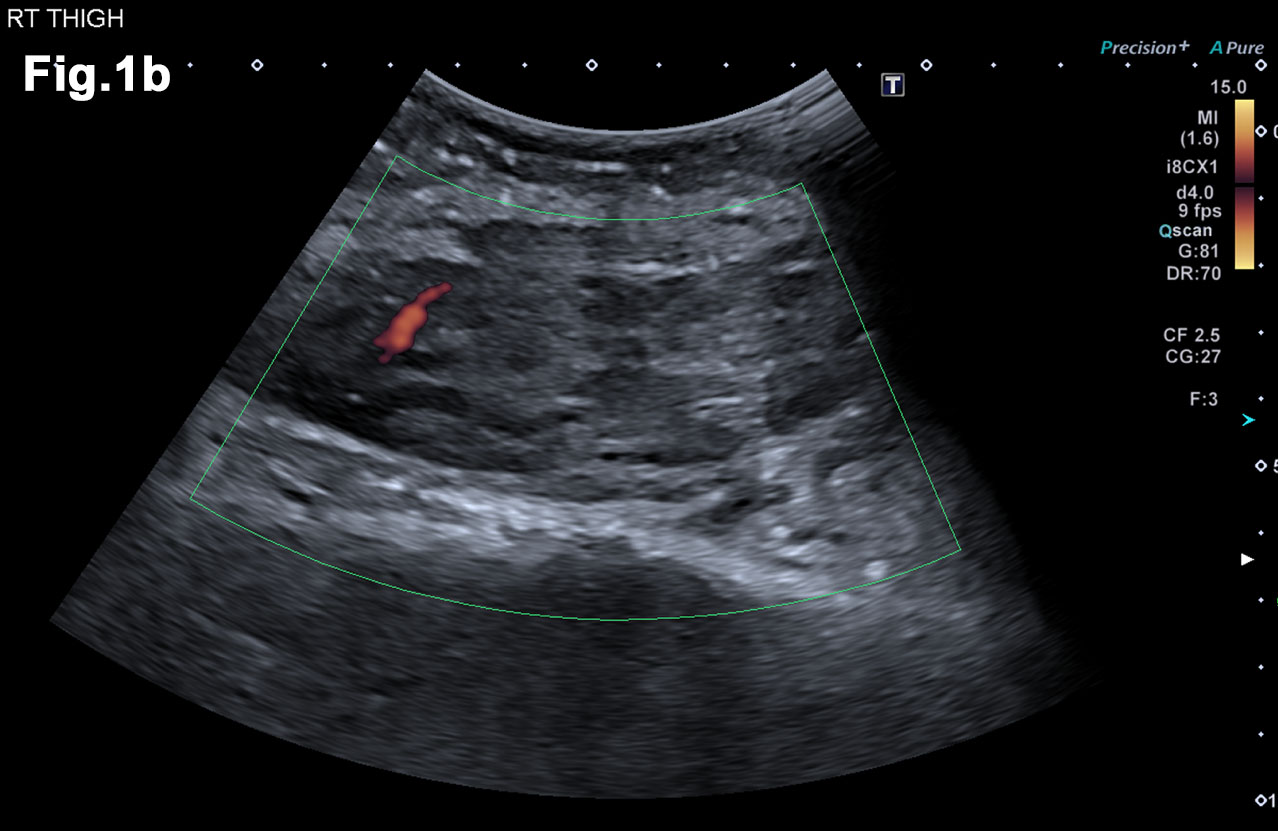

Figure 5 – New presentation of left calf pain with clinical suspicion of a deep venous thrombosis(DVT) – US demonstrated a well-defined hypoechoic mass lesion (a)with moderate vascularity (b) in left gastrocnemius. - Hypoechoic lesion in L gastrocnemius (Fig 5a) - Vascularity demonstrated on Microflow Imaging. (Fig 5b)

- Recent Ultrasound 2018 (Figure 5)

- There was an irregular mass in the left gastrocnemius at the site of tenderness. It was moderately vascular and was subsequently biopsied to reveal a new metastatic deposit similar to the previous lesions and thus disease progression.